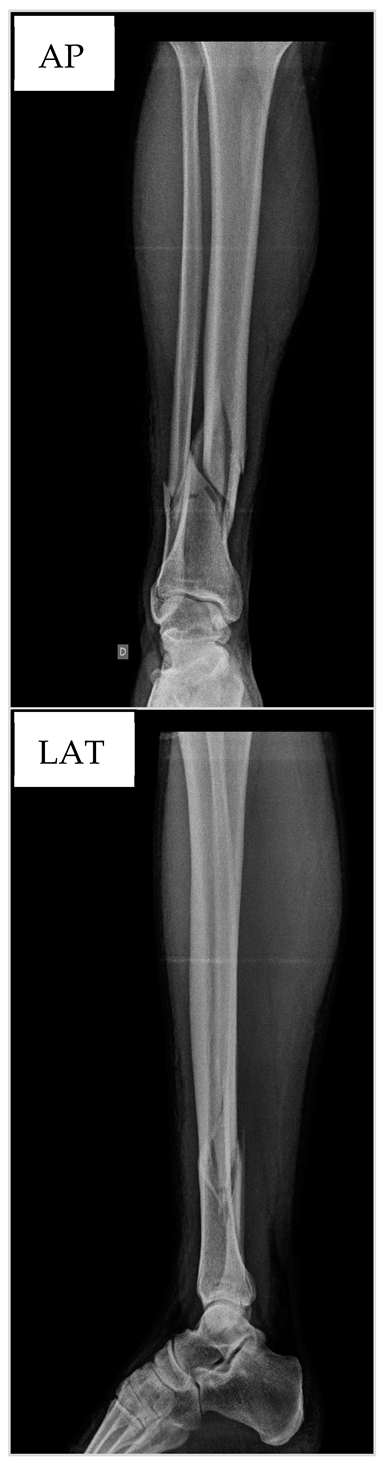

3.1. Patient nº1

3.2. Patient nº2

3.3. Patient nº3

3.4. Patient nº4